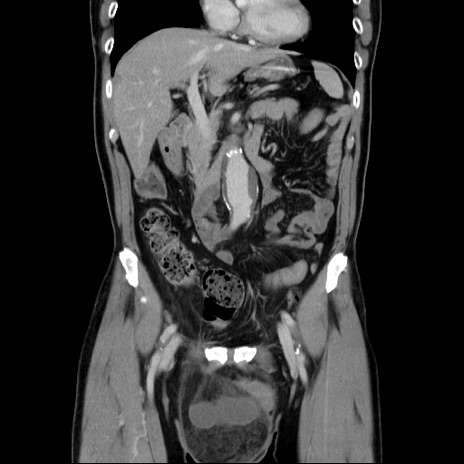

症例34(冠状断像)

【症例】60歳代 男性

【主訴】右鼠径部膨隆

【現病歴】1年程前より右鼠径部膨隆あり。自己にて還納可能だったため放置していた。3時間前より右鼠径部の脱出を認め、還納困難となり受診。

【既往歴】高血圧

【身体所見】右鼠径部に小児頭大の膨隆あり。弾性硬であり、用手還納は困難。左鼠径部にも膨隆を認める。脱出はなし。

【データ】WBC 15500、CRP 測定なし